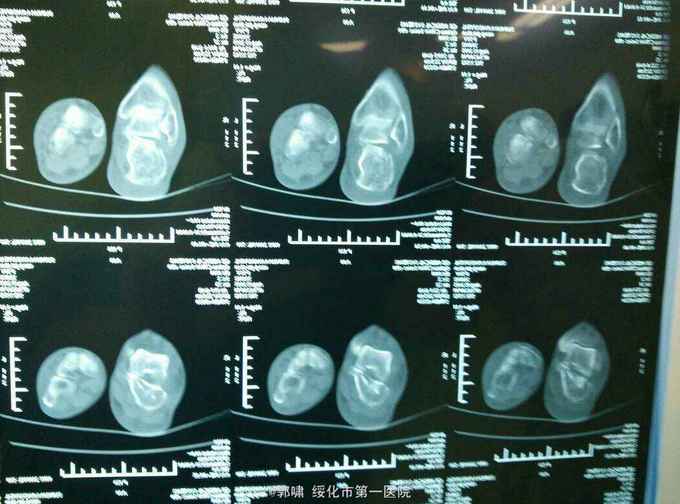

诊断。右跟骨粉碎性骨折。病人入院后常规检查。急诊腰麻下闭合复位。横向挤压恢复跟骨横径。克氏针撬拨恢复跟骨贝雷氏角。恢复跟骨关节面平整。沿跟骨长轴交叉传入细克氏针。拧入空心钉。

跟骨粉碎性骨折。治疗困难。现在治疗方法较多。很多同仁发布了内固定钢板方法。效果很好。但我们基层医院没有类似钢板。急诊应用空心钉。只要掌握技巧。效果也不错。作为补充吧。跟骨骨折必须做到关节面平整。贝雷氏角恢复。跟骨长轴恢复及横径恢复。然后才是固定确实。我最近看了好多内固定跟骨钢板手术。术后效果可能还没有达到理想。闭合复位空心钉内固定就能达到以上效果。缩短手术时间。及医疗费用。患者在二个月就能下地。何乐不为呢?